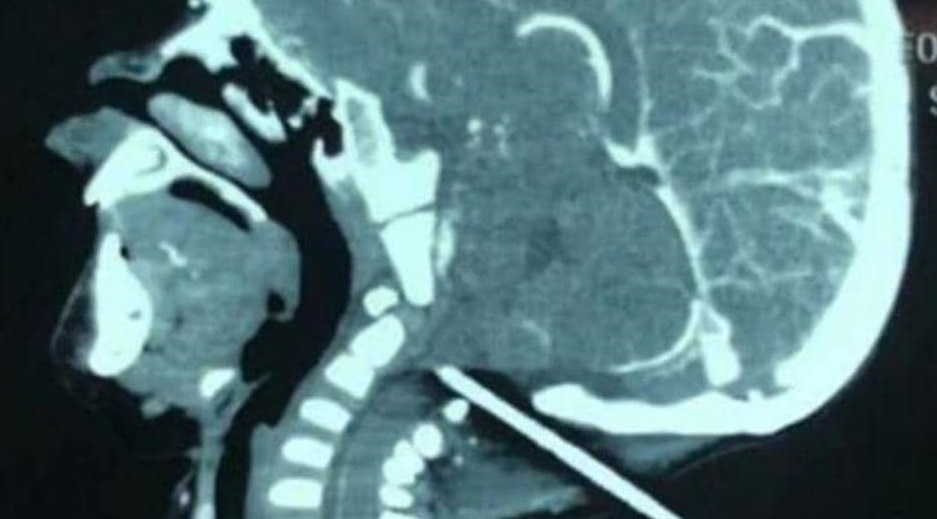

وبعد إخضاع رأس الرضيع للفحص بالأشعة السينية، تبين أن قسماً كبيراً من القصيب مستقر في الجمجمة، ولا يبعد سوى ملليمترات عن الأوعية الدموية في قاع الدماغ.